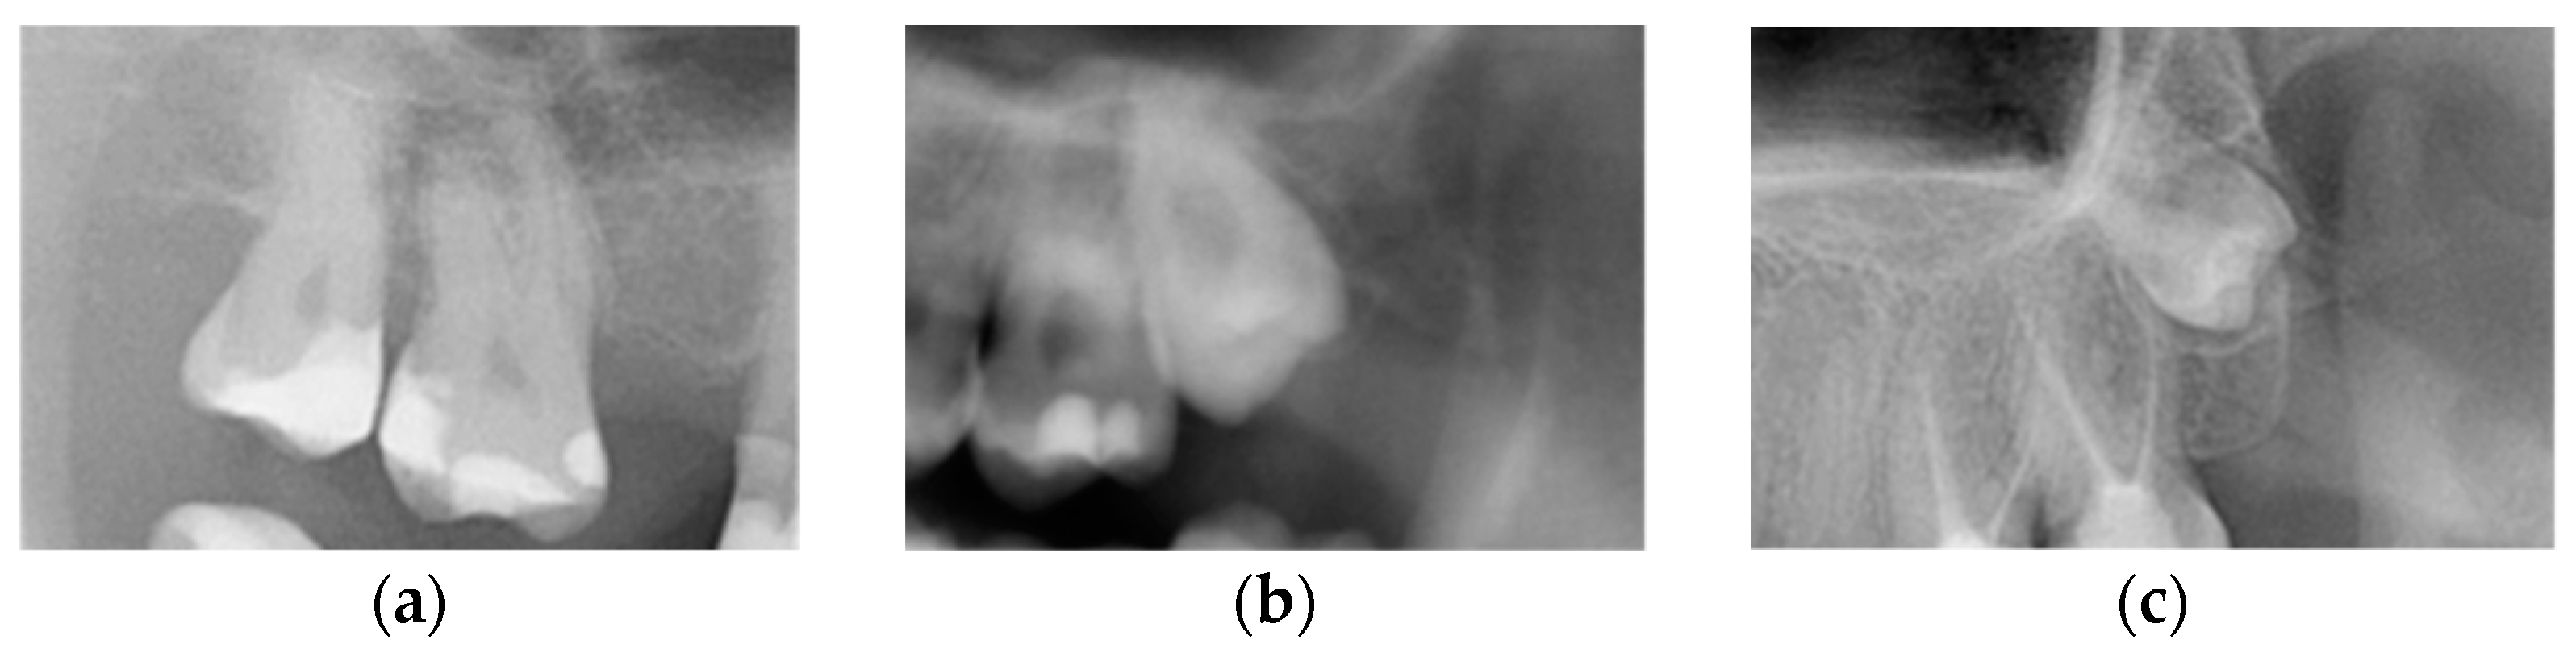

M2s and surrounding tissues were then analyzed for the presence of the following pathologies based on the guidelines by Al Khateeb et al. [24]: (1) caries on the distal surface of the tooth, described as a radiographically clear lesion with no direct contact with the crown of an M3, (2) external root resorption (ERR) on the distal surface of the root, defined as loss of tooth substance, caused by direct contact between M2s and the crown of an M3, (3) alveolar bone loss (ABL) of the alveolar process of the maxilla, or the alveolar part of the mandible distal to M2s, greater than 20% of the length of the distal root (Figure 4).

Figure 4. Radiologic view of pathologies in second molars and adjacent tissues: (a) caries on the distal surface of M2s, (b) external root resorption of the distal root of M2s, (c) bone loss on the distal aspect of M2s.